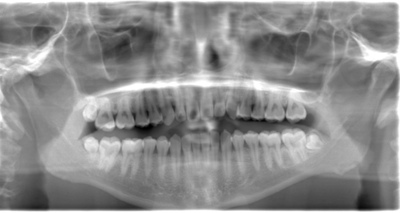

CASE 2

| 年齢・性別 | 30代・男性 |

| 主訴 | 左上下親知らず抜きたい |

| 抜歯期間 | 30分 |

| 抜歯費用 | 約2,500円(保険内) 別途CT撮影で3,000円 |

| 抜歯内容 | 左上下の親知らず抜歯 |

CASE 3

| 年齢・性別 | 20代・男性 |

| 主訴 | 左下親知らず抜きたい |

| 親知らずのはえ方 | 半埋伏 |

| 抜歯内容 | 左下の半埋伏親知らず抜歯 |

CASE 4